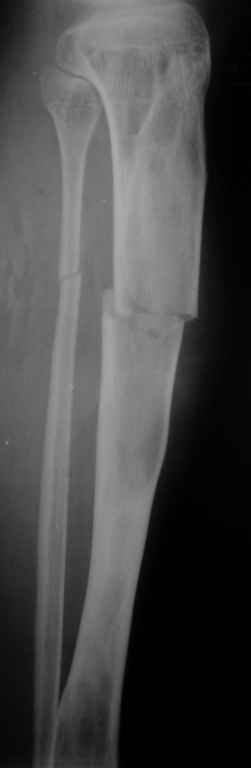

Re: Патологический перелом костей голени.

Вторая проекция.

Если это фиброзная дисплозия, зачем выполнять экскохлеацию? Это не опухоль. Достаточно провести остеосинтез (лучше БИОС). Травма стимулирует остеогенез и произойдет спонтанная оссификация в зоне перелома. Пациент прожил 20 лет без экскохлеации. При полиоссальной форме фиброзной дисплазии не принято радикально лечить один из очагов. Другие все равно останутся. В отношении дополнительной пластики высказаться затрудняюсь, может быть стоит. И если она будет выполняться, следует выполнить и биопсию содержимого полости в зоне перелома для исключения ОБК.

Костная пластика фиброзной дисплазии обречена на неудачу. Ткань фиброзной дисплазии преобладает над нормальной костью через несколько лет. Переломы при фиброзной дисплазии заживают так же, как и обычные. Так что обычного гвоздя будет достаточно. Это защитит кость от переломов в будущем. Вероятность преобразования в остеосаркому порядка 4-ёх процентов. Так что имеет смысл следить за пациентом на протяжении всей жизни.

Доброго времени суток. Всем участвовашим большое спасибо за советы и предложения. Вчера выполнили рассверливание КМК и БОИС большеберцовой кости 11 мм штифтом. С уважением, Евгений.